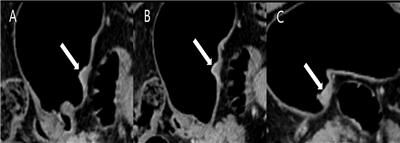

[사진 : 조기위암 T1b sm2/3로 진단 된 환자의 CT 영상. 좌측으로 부터 3단계 조영증강 영상 (동맥기, 문맥기, 지연기)에서 조기위암 (화살표)의 조영증강 양상이 변하는 것을 관찰 할 수 있다.]

CTTM 분석은 CT 영상의 3단계 조영(동맥기, 문맥기, 지연기)에서 종양의 증강 양상을 점수화해 병기를 판별하는 방식이다.